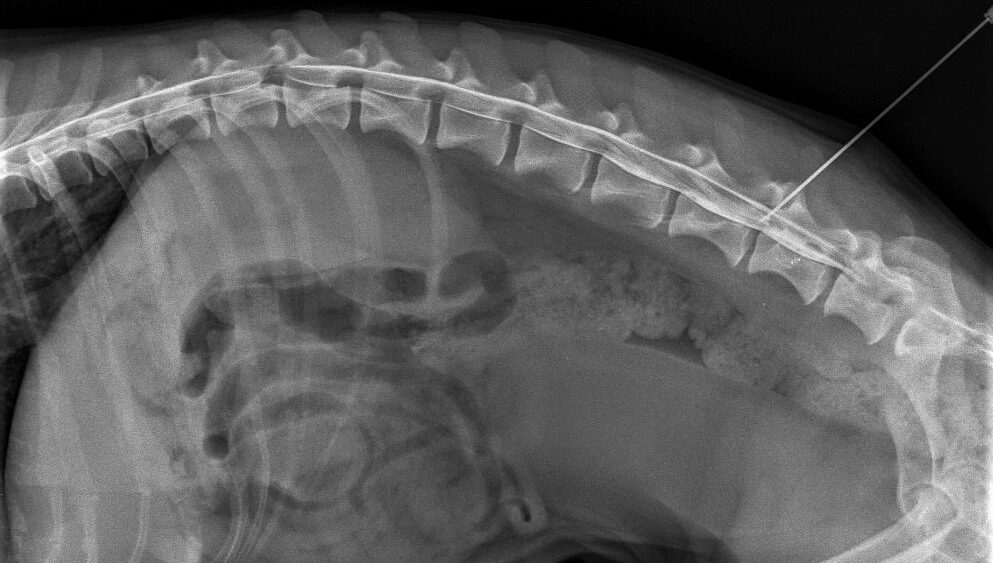

RTG (rentgen)

Rentgenové vyšetření je důležité pro rychlou a přesnou diagnostiku různých zdravotních problémů, jako jsou zlomeniny, degenerativní změny kostí, cizí tělesa, nádorová onemocnění a další abnormality.